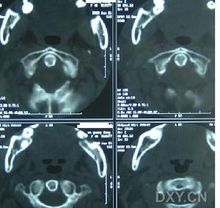

先天性肌斜颈